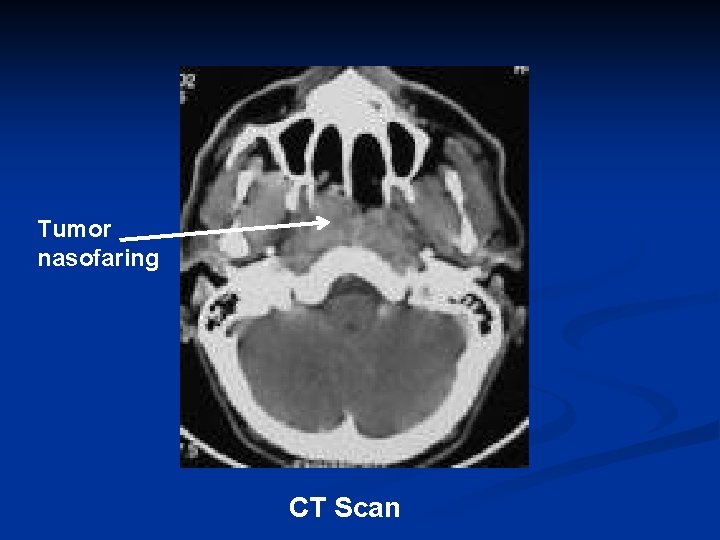

Tumor nasofaring CT Scan